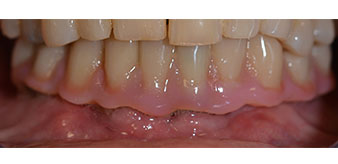

The impression and bite registration were then performed so that the dental technician could begin producing the provisional restoration immediately. This was then screwed in on the same day (Fig. 17 and 18).

Following the time required for the osseointegration, the final impression of the implants could be performed and the final denture produced accordingly (Fig. 19 and 20). At this point, the dentist and patient were able to decide together whether to use a ceramic or acrylic veneer and a zirconium or metal framework. In this case, Dr. Pascu’s team decided on an acrylic veneer based on the unclear prognosis for the maxillary dentition and the fact that tooth 24 is elongated. This type of veneer is generally considerably easier to adapt and can thus be subsequently altered to reflect the new situation in the maxilla.